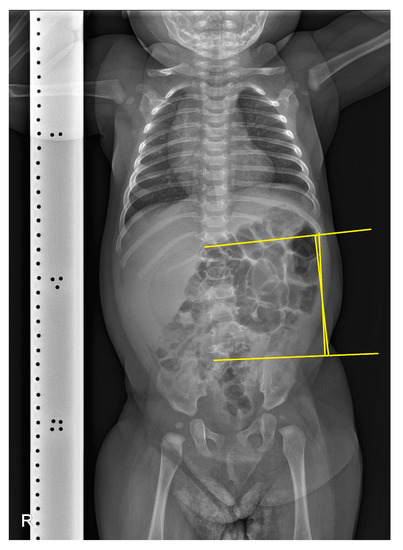

A simple radiographic evaluation was performed to identify any other related complications. To rule out vertebral anomalies, particularly high cervical vertebrae deformations—which could be a cause of congenital torticollis—we examined the cervical spine [9]. The cervical spine simple radiograph was obtained in the anteroposterior view and lateral-extension view (Figure 3). No bony abnormalities or airway obstructions were detected. Whole-spine simple radiography revealed mild right-side thoracolumbar scoliosis (Figure 4). The Cobb angle of the thoracolumbar curve was 12 degrees. Both scanography and pelvic simple radiography revealed no abnormalities in the lower limb and hip regions.

Figure 4. Whole-spine simple radiography. The yellow lines indicate the Cobb angle of the thoracolumbar curve, which measures 12 degrees, suggesting mild thoracolumbar scoliosis.